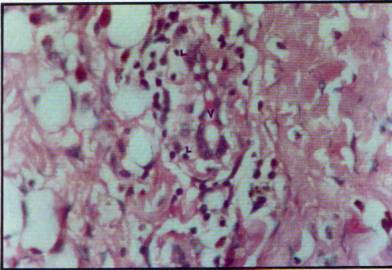

Foto

11: Estructura venular de pared endotelial gruesa (V) con linfocitos que

atraviesan

Los neovasos presentaron en áreas aparentemente más antiguas, paredes

delgadas y tejido conectivo hialino perivascular, adoptando además la foriria

de lagos extensos y delgados interconectados (foto 13).